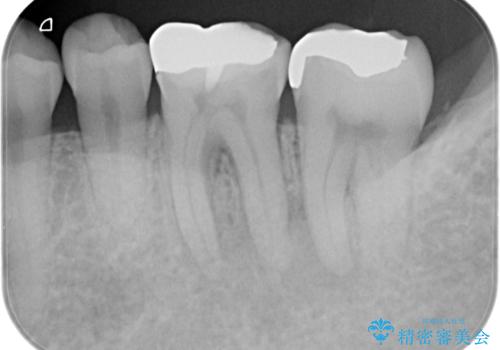

- 噛んだ時の痛みを主訴に当院受診されました。

根管治療を行なったのち、症状改善を認めオールセラミッククラウンにて修復治療を行なっております。

┌7は今回の治療後打診(-)、正常歯髄へ診断のもと経過観察を行なっております。